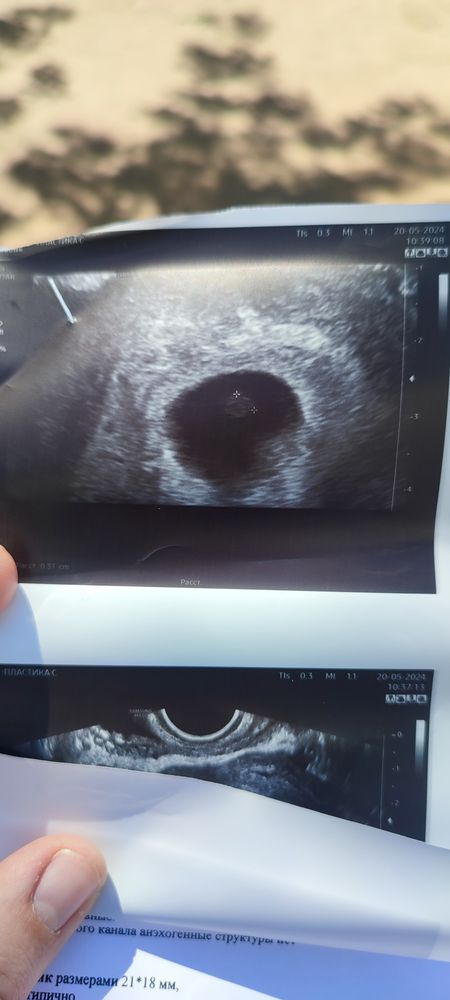

Девочки,месячные были 2.04 , овуляция по тестам 24.04, Сегодня была на УЗИ ,В понедельник была прошлый было плодное яйцо 4,5 мм,а сегодня 18мм и желточный мешочек 3мм, эмбрион не видит,сказала динамика хгч и УЗИ нужна сдала кровь щас , будет готов через пару часов(пришел 18779),а УЗИ в пятницу записалась ,если ничего не будет видно опять но все....(((,по калькулятору беременности вроде все нормально,но врачу не понравилось,как и мне я вся в напряжении...

У меня в 6.1 было пя 13 мм и жм 3,5 мм, в 7.1 был эмбрион с ктр 6 мм и сердцебиением, дочка в сентябре уже в сад пойдет) Для 5.5 у вас все хорошо, ждите без паники неделю до пя 25 мм, тем более желточный мешок у вас уже есть. У вас отставание в неделю так и будет тянуться, потому что стандартно считается, что овуляция была на 14 день, а у вас на 23.